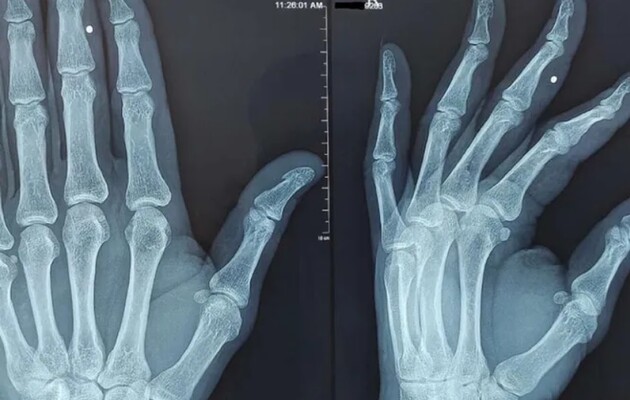

Лікарі поставили їм діагноз «синдром фіброміалгії». Це ще один довгостроковий стан, який пов'язаний з болем у всьому тілі та скутістю м'язів. Рентгенівські знімки показали наявність у кістках деяких пацієнтів відростків, схожих на шпори. У пацієнтів також спостерігалася нестача вітаміну D.